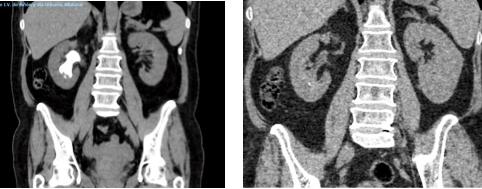

1) The lack of recognition of high volume and highly qualified centres; 2) The lack of agreement among surgeons regarding surgical procedures and the management of complications; and 3) The absence of a long-lasting and beneficial partnership between patient associations and the Uro-andological Scientific Society are the unmet needs for bettering the care of transgender individuals who need gender-affirming surgery

In conclusion, it is clear that gender dysphoria is a complicated mental illness that requires specific treatment such as several times gender-affirming surgery The question not is: “So, what is the reason for this insistence on GAS?” but “How we can improve the management of gender-affirming surgery in terms of quality of care, patients’ satisfaction and quality of life?”

REFERENCES

1 Bayraktar Z Urogenital and extra genital mutilation in gender-affirming surgery: Are we violating primum non nocere? Arch Ital Urol Androl 2025; 97:13324